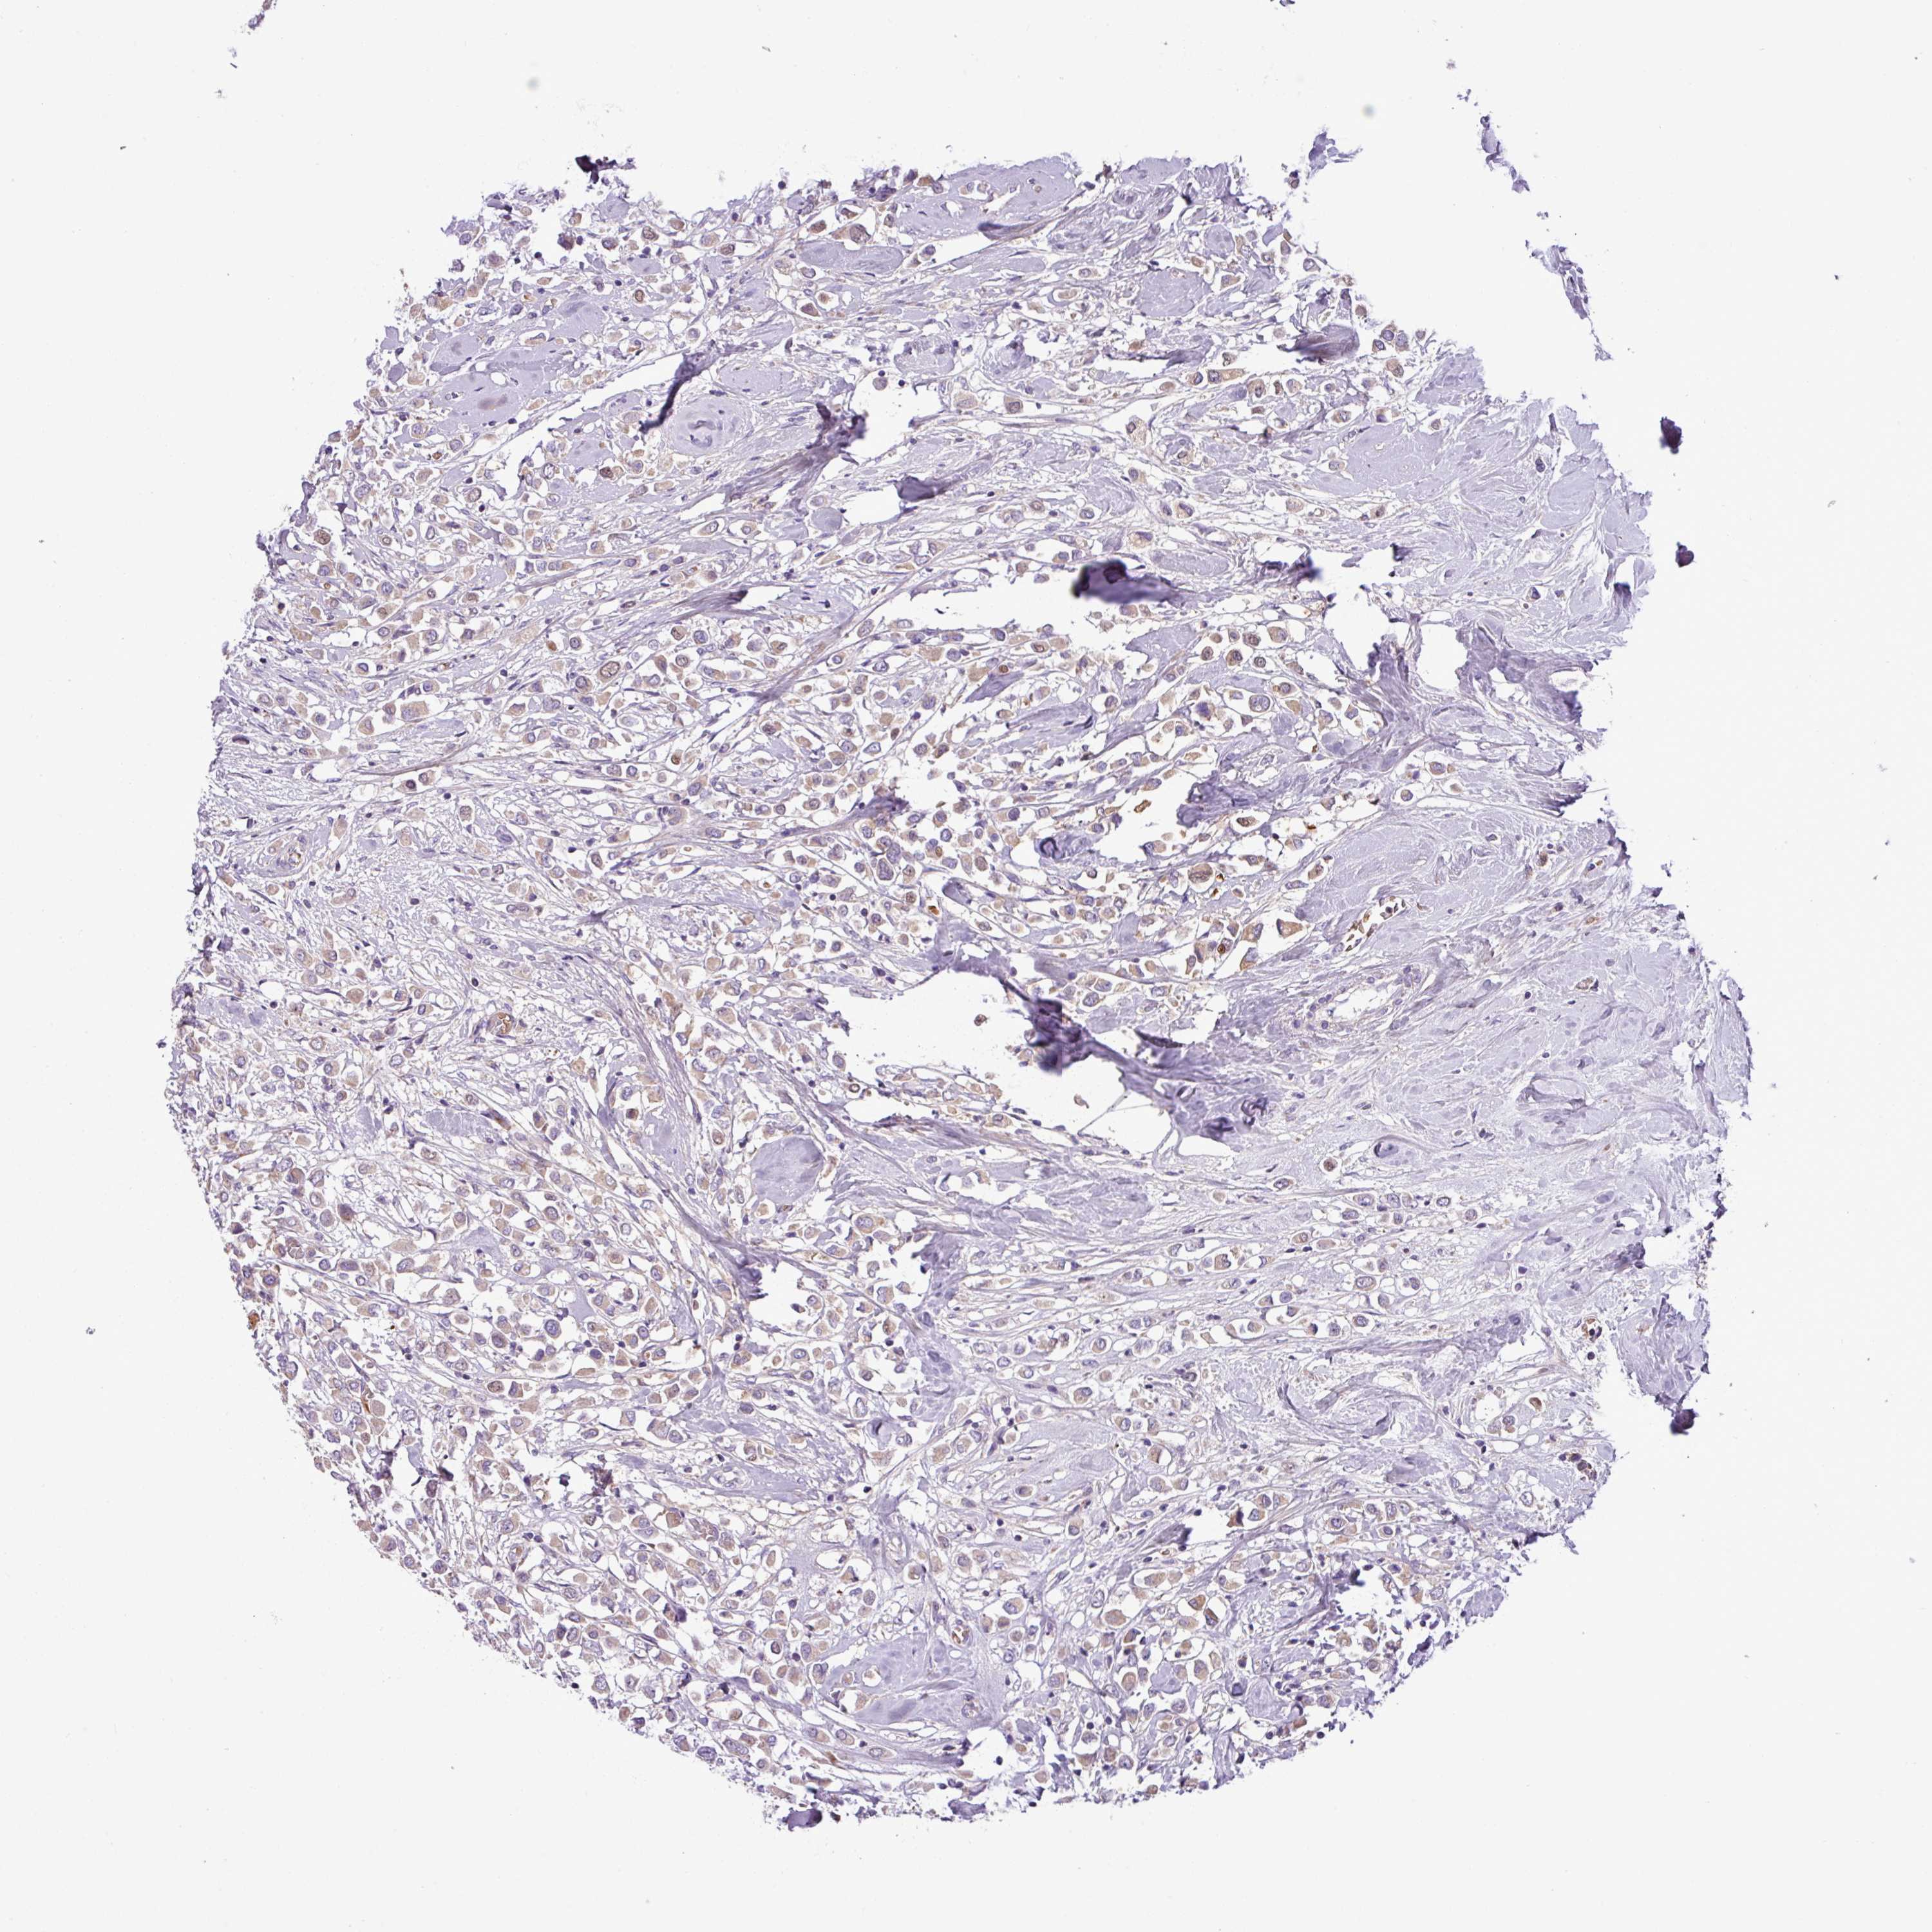

CANCER BREAST CANCER Show tissue menu

BRCA TCGA BRCA VALIDATION PROTEIN EXPRESSION

Breast cancer

Human cancer

Breast invasive carcinoma

FAM183A is not prognostic in Breast Invasive Carcinoma (TCGA)